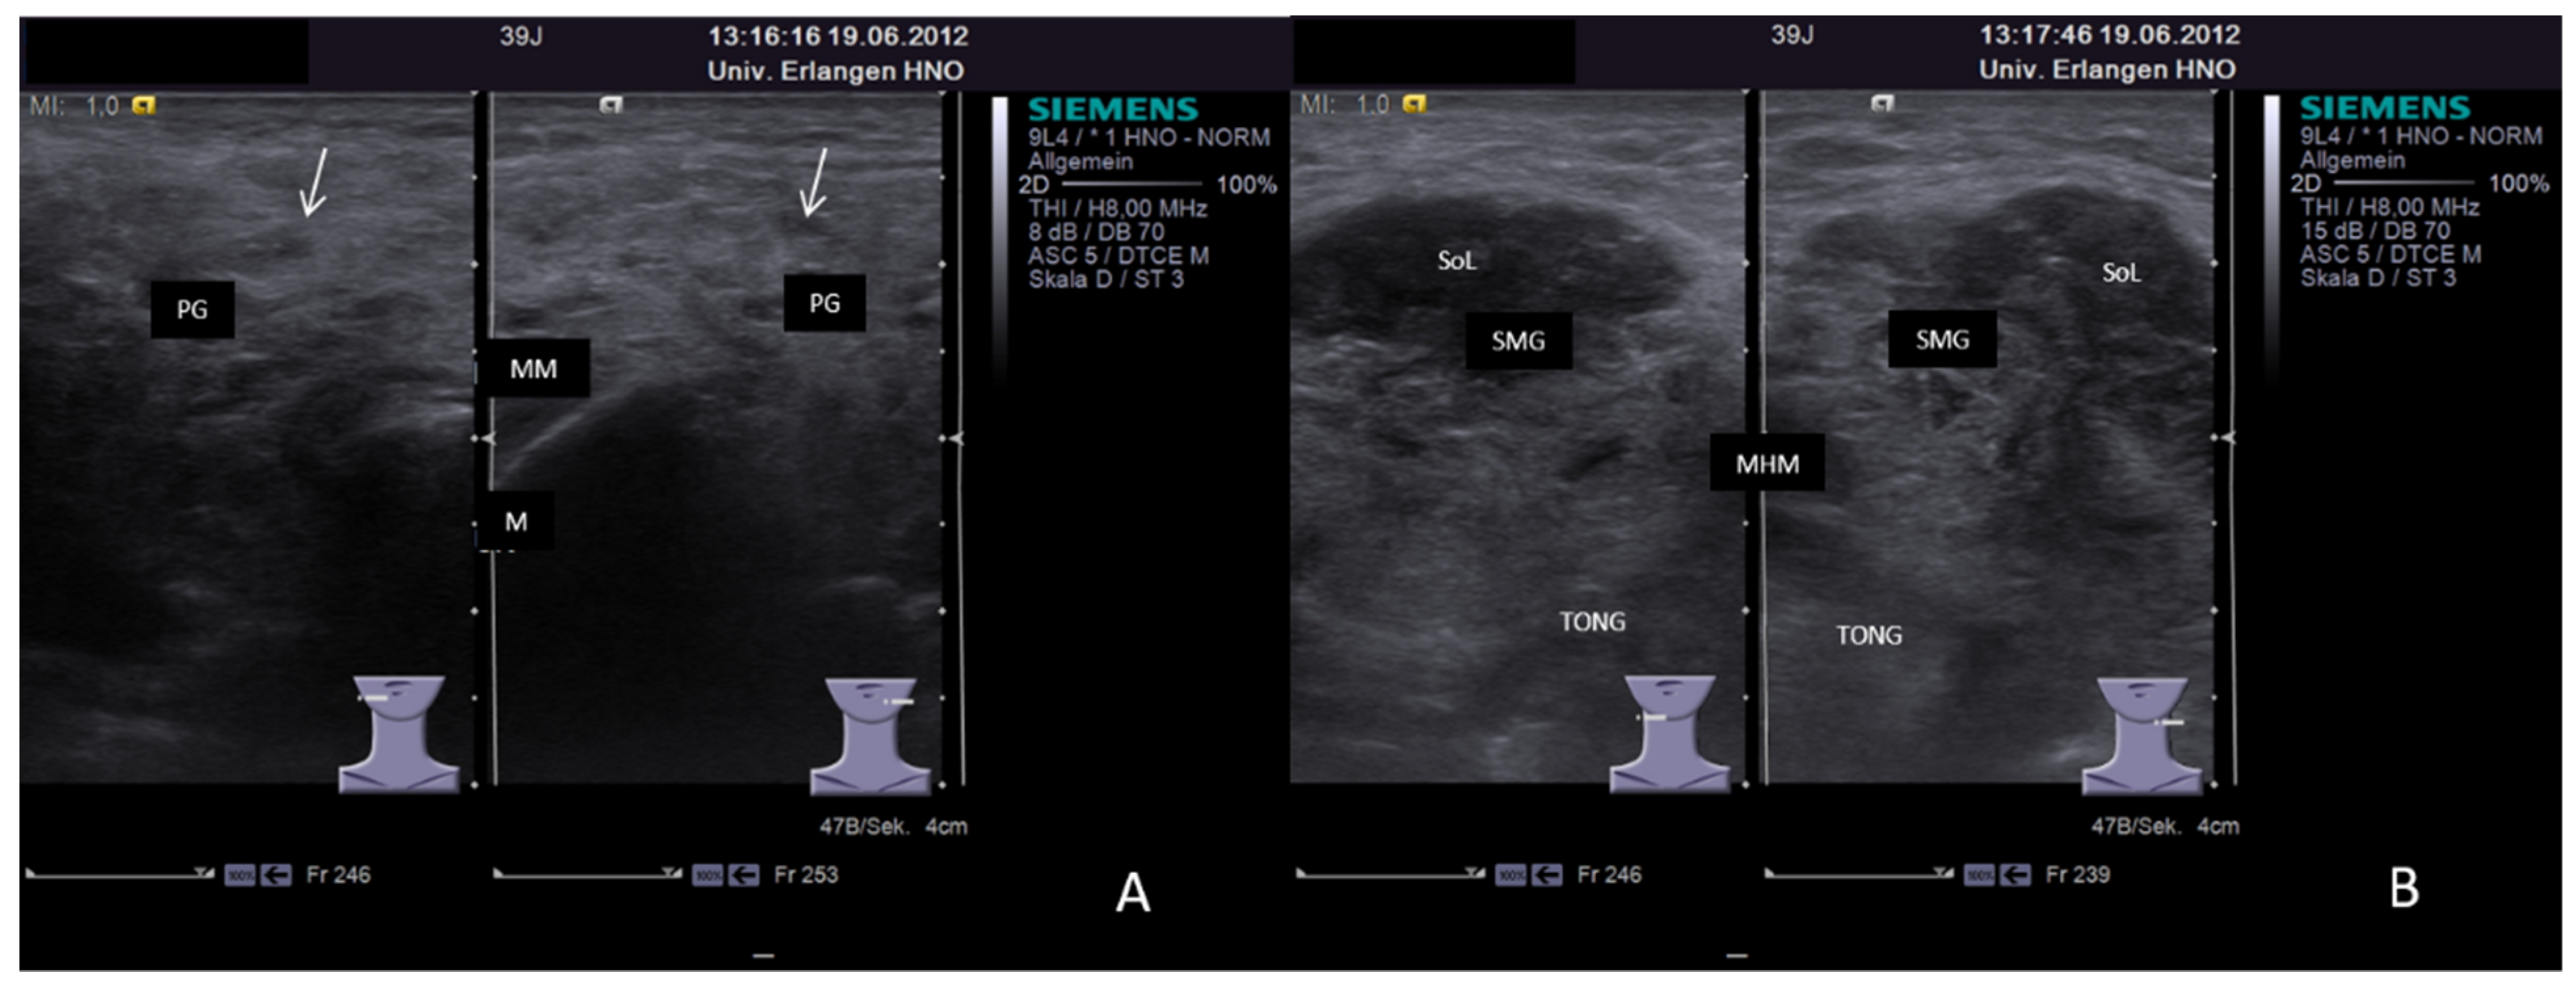

3.2. Findings in Normal Anatomy in Major Salivary Glands

3.3. Ultrasonographic Signs of Acute and Chronic Inflammatory and Obstructive Sialadenitis

3.3.1. Acute or Subacute Primary Non-Obstructive Microbial Sialadenitis